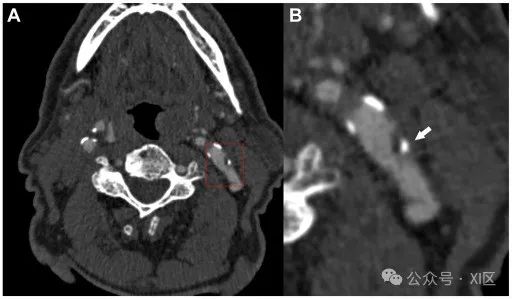

虽然关于钙化在动脉粥样硬化中的功能仍有争论,但钙化的大小、形状和位置等因素可影响斑块形成的进程,这一点已被广泛接受,最近的一些论文显示,在某些情况下,这些因素与斑块的易损性及随后的卒中风险相关。特别是,阳性边缘征(positive rim sign)与斑块炎症、血管渗漏和IPH的形成密切相关。一项针对329名无症状颈动脉斑块的鹿特丹人群研究患者的前瞻性队列研究显示,较高的钙化负荷与IPH的存在相关。CT扫描被认为是检测斑块内钙化的参考标准(图4)。但值得注意的是,斑块钙化也可通过US检查和MRI检查发现,前者表现为高回声区,后者在所有对比序列上都表现为低信号区。

图4 CT显示的不同类型颈动脉钙化示例。(A)颈动脉斑块伴浅表钙化(白色箭头)。(B) 颈动脉斑块伴有大块钙化(白色箭头)。(C) 颈动脉斑块伴阳性边缘征(白色箭头)。颈动脉蹼